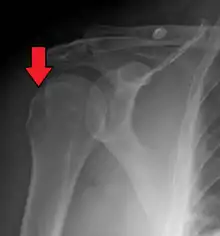

Hill–Sachs lesion post-shoulder dislocation

X-ray at left shows anterior dislocation in a young man after trying to get up from his bed. X-ray at right shows same shoulder after reduction and internal rotation, revealing both a Bankart lesion and a Hill-Sachs lesion.